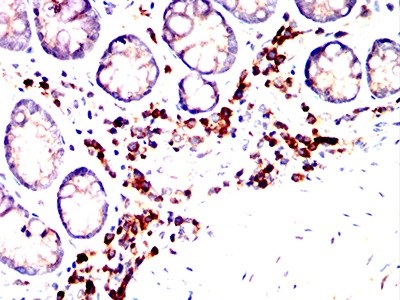

发布时间:2026-01-12 15:24:38基质金属蛋白酶9(MMP9)作为基质金属蛋白酶家族的重要成员,通过降解细胞外基质参与诸多生理与病理过程。其异常表达与活性失调关联慢性炎症、肿瘤发生发展及转移等多种病症,成为具有潜力的治疗靶点。抗体药物凭借抗原特异性结合优势,在MMP9相关疾病干预中展现独特价值。人源化改造是抗体走向临床应用的核心环节,可显著降低免疫原性,提升药代动力学特性与临床安全性。以下将解析人源化MMP9抗体开发的关键要点。